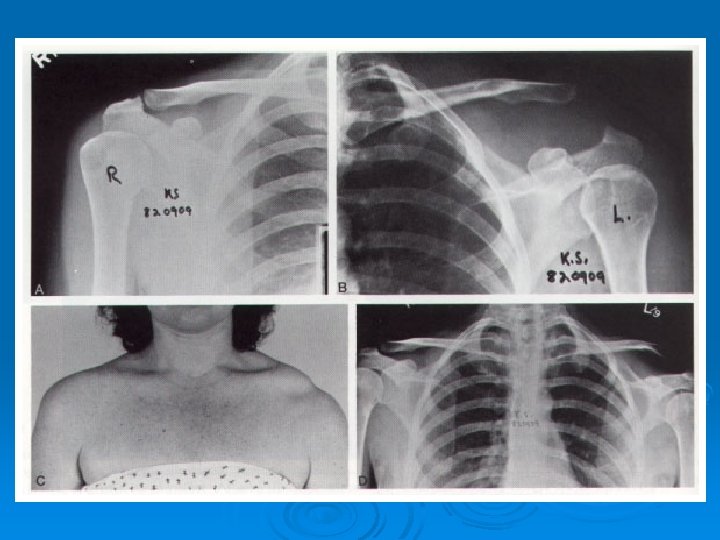

Acromioclaviclular Separation Ø Usually due to direct trauma- Superolateral aspect of the shoulder Ø Player striking the ground Ø the acromion is forced inferior relative to the clavicle

CLASSIFICATION Ø Type I AC ligament sprain l AC joint intact l CC ligament intact l Deltoid and Trapezius muscles intact l

CLASSIFICATION Ø Type II AC joint disrupted l CC ligament sprain l Deltoid and Trapezius intact l

CLASSIFICATION Ø Type III AC ligaments disrupted l AC joint dislocated l CC ligaments disrupted l Deltoid and Trapezius detached from distal clavicle l

CLASSIFICATION Ø Type IV AC/CC ligaments disrupted l Clavicle displaced posteriorly into or through Trapezius l

CLASSIFICATION Ø Type V AC/CC ligaments disrupted l Gross disparity btw clavicle and scapula l Deltoid and Trapezius detached from distal half of clavicle l

CLASSIFICATION Ø Type VI AC/CC ligaments disrupted l Clavicle displaced inferior to acromion or coracoid process l

DIAGNOSIS Ø History Ø Mechanism of Injury Ø Physical Exam Ø Radiographs

Nonoperative Treatment Type I and II l More than 35 different forms of management l Sling 10 -14 days, early and gradual PT l Heavy lifting and contact sports avoided for 8 -12 weeks l

Operative Treatment Ø Grade III +/-, in younger, active Ø Grade IV, V and VI patients